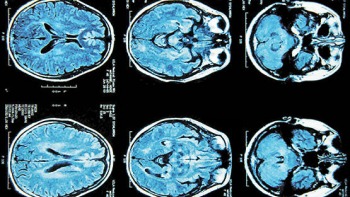

El glioma, una forma de cáncer cerebral mortal en la mayoría de los casos, podría estar vinculado a la inactividad física realizada durante la adolescencia, según un estudio del Instituto Nacional del Cáncer de Estados Unidos que publicó la revista Cancer Research.

Los gliomas son el tipo más común de cáncer cerebral, constituyen casi el 80 por ciento de los cánceres del cerebro y el sistema nervioso central. Aunque se sabe poco sobre sus causas, algunas evidencias sugieren que exposiciones ambientales durante la infancia y la adolescencia podrían tener un importante papel en su origen.

Imagen